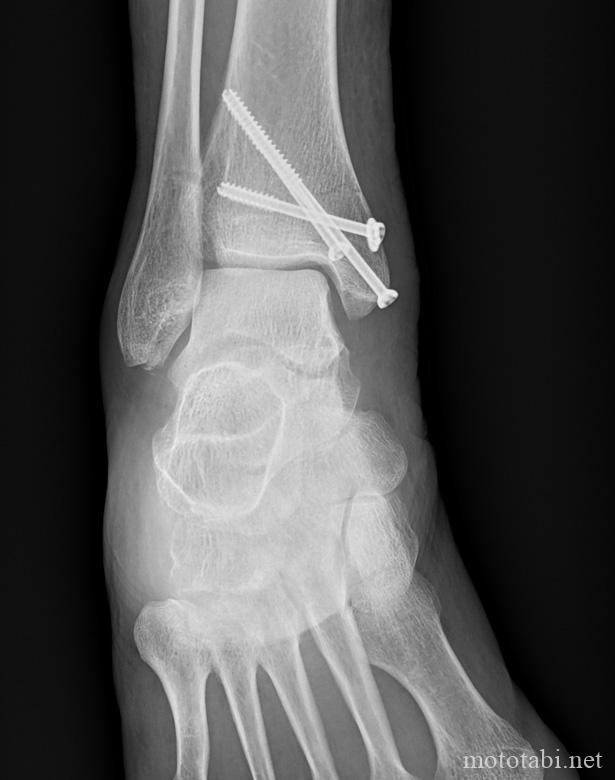

2019年9月、山梨県のクリスタルラインを走行中に転倒し、足首を骨折しました。

足関節骨折した日から5日目に入院し、ボルトを入れる手術をしました。

ボルトはそのままでも問題がないと説明がありましたが、私の場合はくるぶしあたりが痛くなることがあります。1年前に病院でレントゲンを撮ったとき、ボルトがゆるんでくるぶしあたりに当たっていると言われました。

レントゲンの結果

レントゲンの結果、1年前とボルトの位置は変わっていないそう。

緊急に手術する必要はないけれど、いずれ手術することにしました。

ただし、私が手術した病院は現在手術を行っておらず、東京の別の病院か他の病院かの2択。地元に近い東京の方が良いのではないかなと思い、東京の他の病院への紹介状を書いてもらいました。その他、今までのレントゲン結果をデータでもらいました。